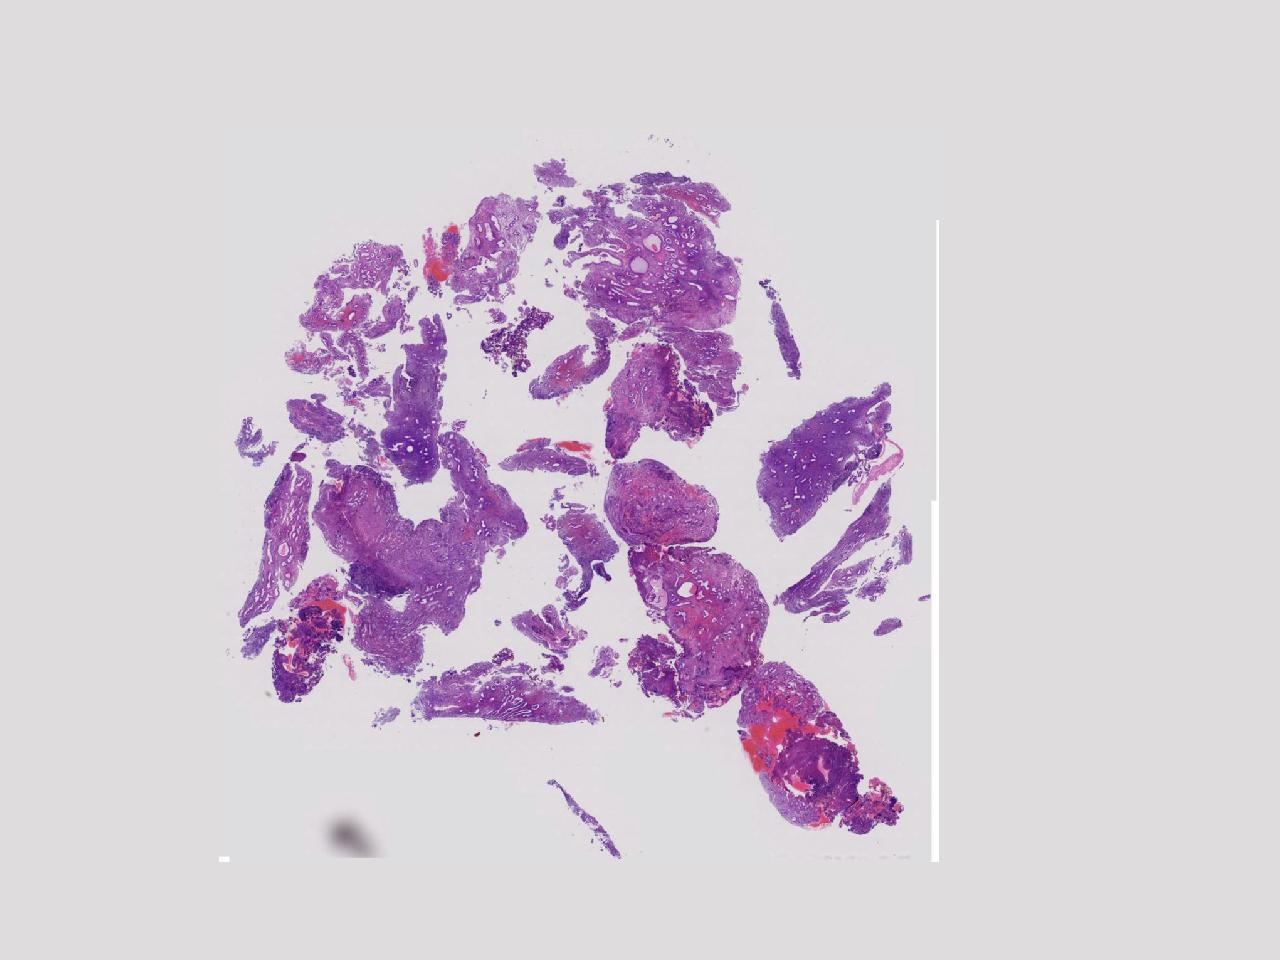

性别

女

年龄

55岁

女,55岁,月经紊乱4年,彩超示:子宫内膜增厚(内膜厚15.7mm),末次月经:2025年7月27日。

标本名称

宫腔镜下子宫内膜活检

大体所见

灰粉色不整形软组织多块,1.5X0.8X0.6厘米。

图1